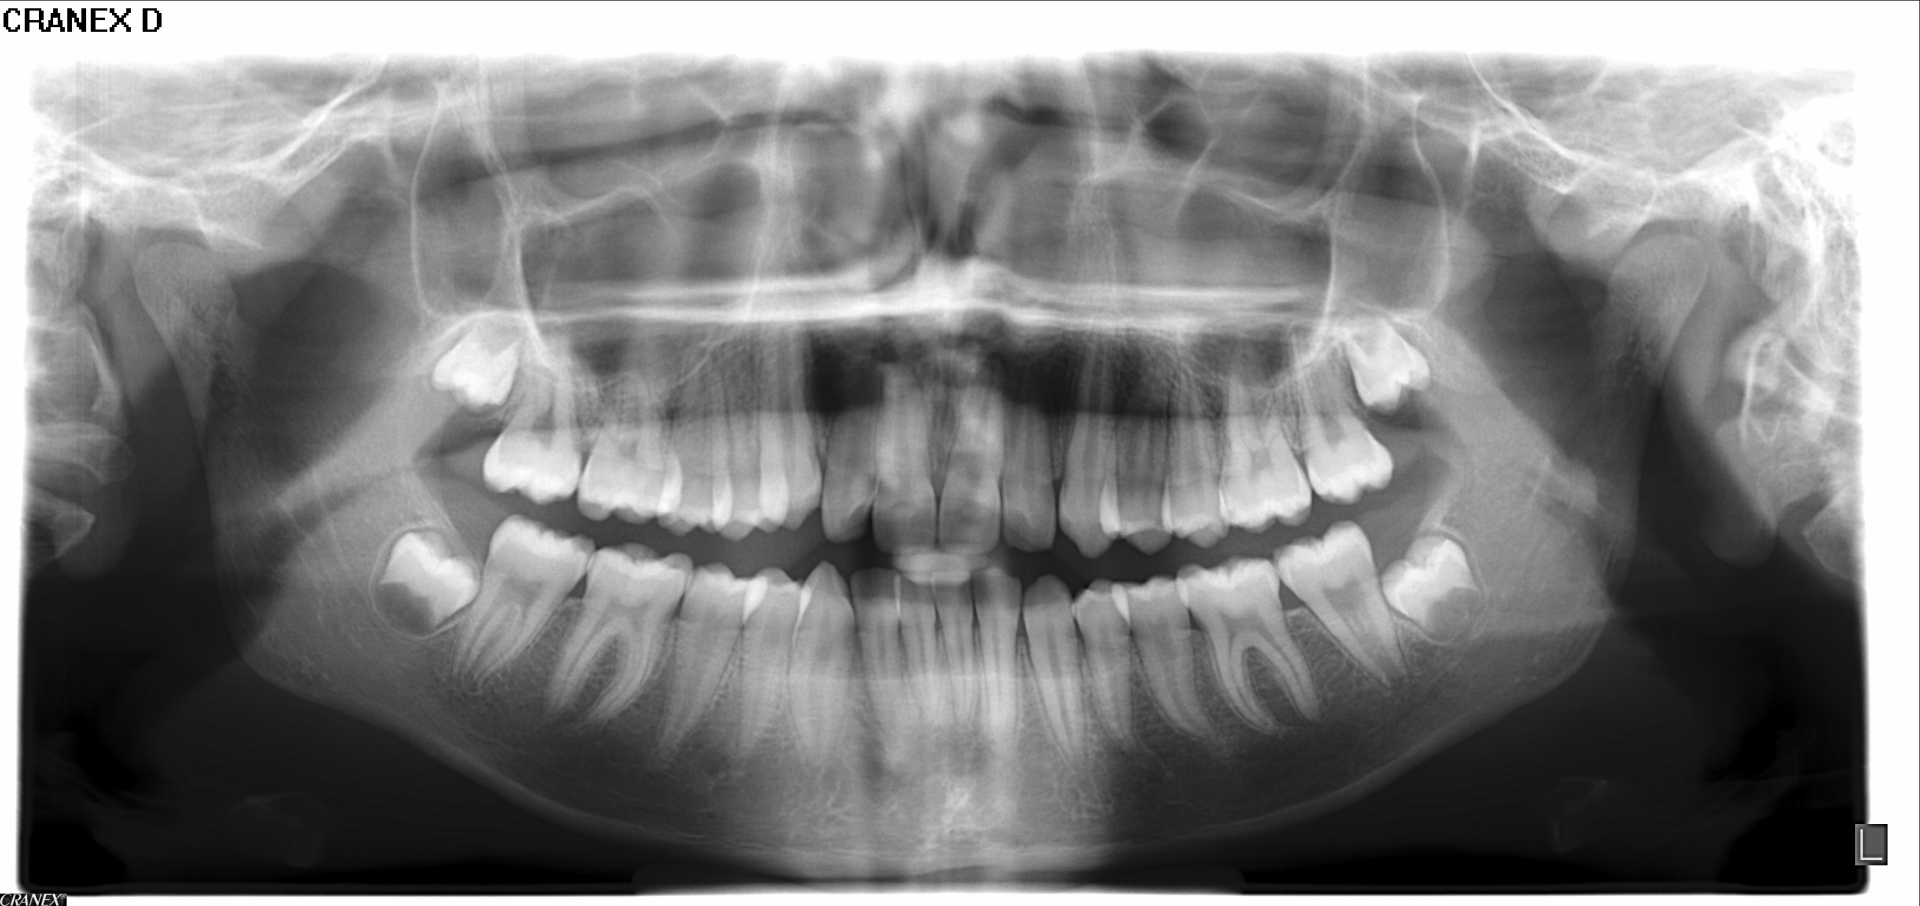

ORTOPANTOMOGRAFIAS: ( Rx Panorámica)

Son radiografías de las dos arcadas, boca completa, y ofrece una vision generalizada de todas las estructuras óseas, dentales y articulares. Estas pueden ser

frontales o

laterales.